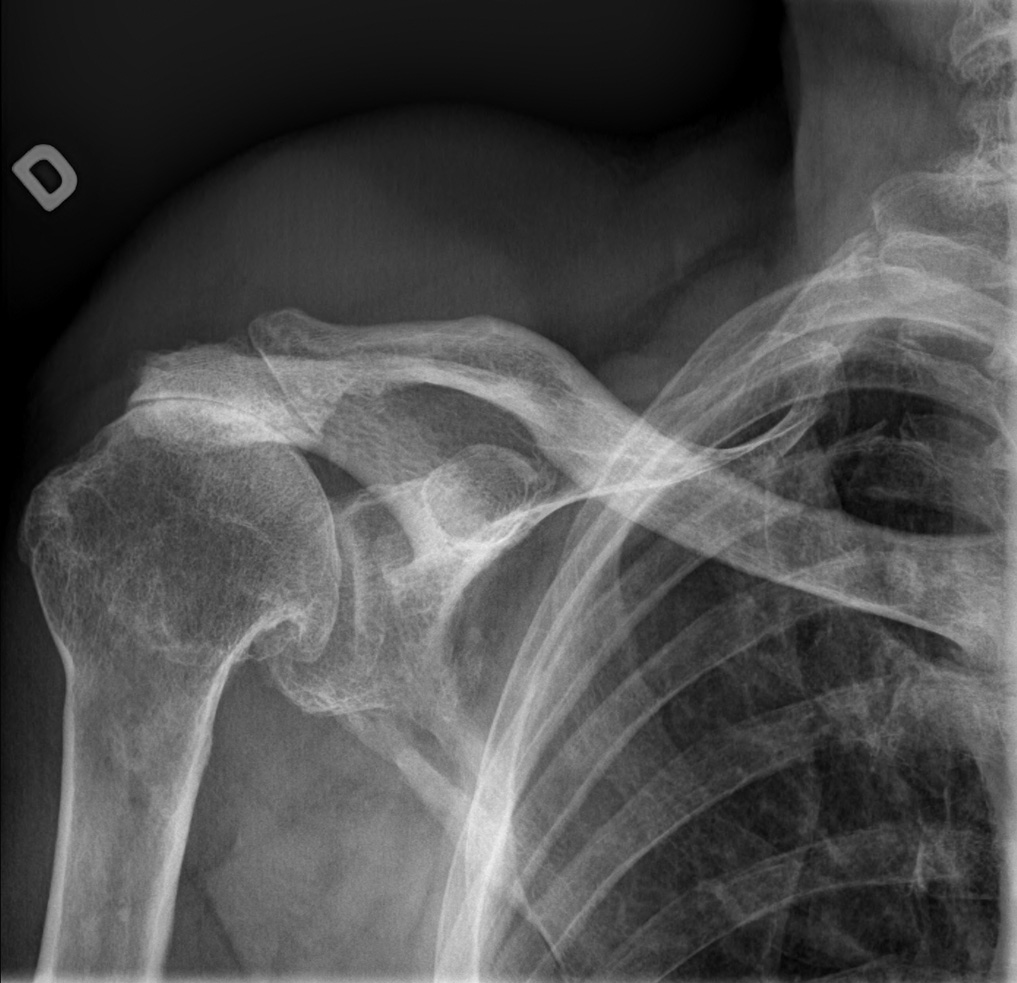

71-year-old male:

Right shoulder pain and stiffness.

Glenohumeral arthrosis

Bone irregularities

Degenerative changes of the right glenohumeral joint with joint space narrowing and inferior ostephytes formation. Joint space narrowing assessment would be better on a true anteroposterior view of the shoulder joint instead of the thorax, as is the case here.

Acromioclavicular arthrosis

Severe acromioclavicular osteoarthritis with joint space narrowing and osteophytes.

Glenohumeral alignment

On the scapula lateral view (trans scapular view), the humeral head is well positioned in front of the glenoid (middle of the "Y"), thus eliminating a gleno-humeral dislocation.